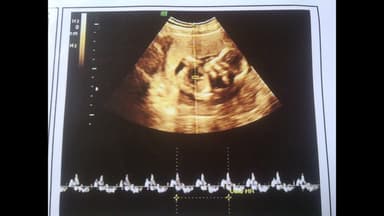

Vào tuần thứ 6-7, mẹ bầu có thể lần đầu được nghe tiếng tim thai đập trong bụng mình.

Thai nhi mấy tuần có tim thai? Khoảng 21 ngày sau khi thụ thai, trái tim bắt đầu nhịp đập đầu tiên. Nhịp tim được phát ra từ các sợi cơ tim. Các xung điện di chuyển khắp ống tim nguyên thủy để bắt đầu nhiệm vụ suốt đời đó là duy trì não bộ và các cơ quan quan trọng khác. Trong khi tim bắt đầu đập ở tuần thứ 4-5, các mẹ thường không nghe được nhịp tim thai khi siêu âm, phải đến tuần thứ 9 hoặc 10 mới mới nghe được. Và đến tuần 20, mẹ sẽ nghe được tim thai bằng ống nghe bình thường. Thai máy bao nhiêu lần một ngày

Ở tuần thứ 7, tim thai bắt đầu phân chia thành buồng trái và phải. Bác sĩ có thể nhìn thấy và đo được những điểm sáng nhấp nháy trên máy siêu âm. Ở giai đoạn này, nhịp tim của bé rơi vào khoảng 90-110 nhịp/ phút. Nhịp tim của bé đạt đỉnh cao nhất vào khoảng tuần 9, từ 140-170 nhịp/phút. Các tuần thai sau này, tim của bé sẽ hoàn chỉnh hơn về cấu tạo và chức năng cũng như kích thước. Giai đoạn này, nhịp tim của bé sẽ vào khoảng 120-160 nhịp/ phút.